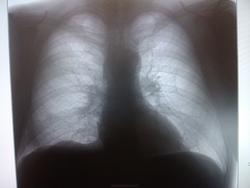

Пациент, 50 лет. Мед. осмотр. (извиняюсь за качество). Какие будут мнения?

май 2014 г.

Сначала ветку целиком не открыла, думала вопрос касается только первого снимка, высмотрела подозрительную тень на уровне 5 ребра, и правый корень не понравился. С учетом продолжения однозначно периферический

Пермферический рак нижней доли правого легкого в S9-10(учитывая отрицательную динамику за год)

Согласна с коллегами. Справа в S 10 периферическое образование, учитывая рост, более вероятно  C-r.  Cлева в среднем поле   воздушная киста

Господи! Какой ретроспективный анализ? Она-оно (зло) растет себе и растет, кстати, на фоне этих кист в обоих легких ( Nobody, Вам-особенный респект!)